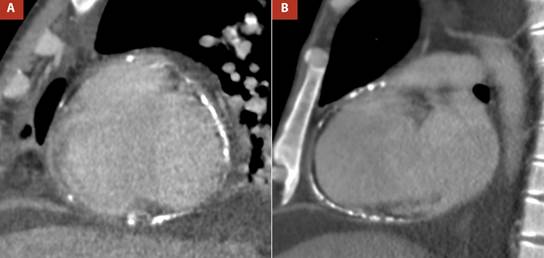

The most important evidence in the transesophageal echocardiography (TEE), was the inability of both ventricles to achieve complete distensibility due to the surrounding pericardial shell, which led to an arrowhead morphology of the heart (Figure 2A andVideo 1). The pericardial thickness was measured at 7 mm in the right atrial wall, which also presented a notorious limitation in its distensibility (Figure 2B and Video 2).

Figure 2 A. Two-dimensional TEE 4 cameras. Thickened pericardium (white arrows) is visualized, which markedly limits ventricular compliance, causing the ventricles to present an arrowhead morphology, B. Orthogonal TEE images, focused on the lateral wall of the right atrium with calcification evident by posterior acoustic shadowing, the pericardial thickness was 7 mm (white arrows).